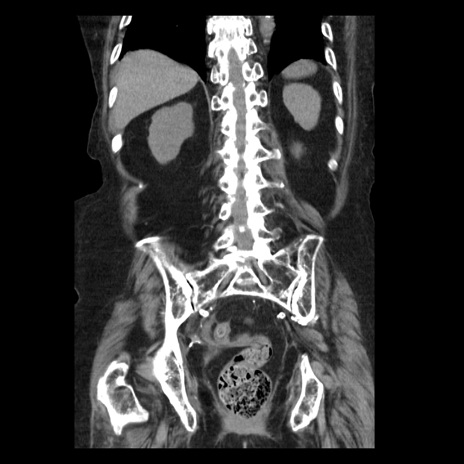

症例14(冠状断像)

【症例】 90歳代女性

【主訴】 腹痛・嘔吐

【現病歴】今朝から左側腹部痛を認めた。 経過観察していたが、嘔吐を認めたため来院。

【既往歴】 子宮癌術後

【身体所見】 意識清明、BP 127/54mmHg、P 98bpm Sp02 95%(RA)、BT 35.8°C、腹部平坦・軟腸ぜん動音聴取良好、右下腹部圧痛(+) 反跳痛なし

【データ】WBC 9800、CRP 0.46